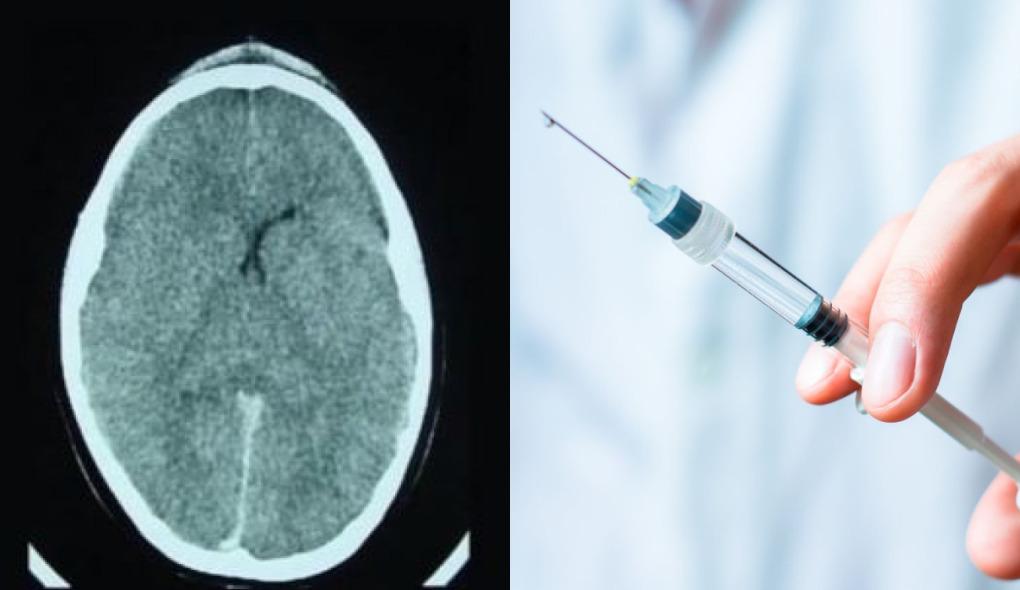

Uma jovem de 20 anos foi internada em estado grave após colocar o implante "chip da beleza" com ocitocina. O caso aconteceu em São Paulo e foi exposto nas redes sociais.

Segundo ele, a mulher deu entrada no hospital menos de 24 horas após o implante com "quadro de rebaixamento de consciência e convulsões, edema cerebral e diminuição dos níveis sanguíneos de sódio".

No caso da jovem de 20 anos, o implante possuía mais de mil unidades. O médico acredita que ela sofreu uma intoxicação hídrica devido ao uso excessivo de ocitocina.

Segundo ele, o hormônio levou a uma diminuição do sódio e resultou num desequilíbrio hidroeletrolítico. "Foi tentado sem sucesso a retirada do implante. Ela está estável, mas sem prognóstico definido. Vamos torcer para que a recuperação seja plena e rápida!", declarou no Instagram.